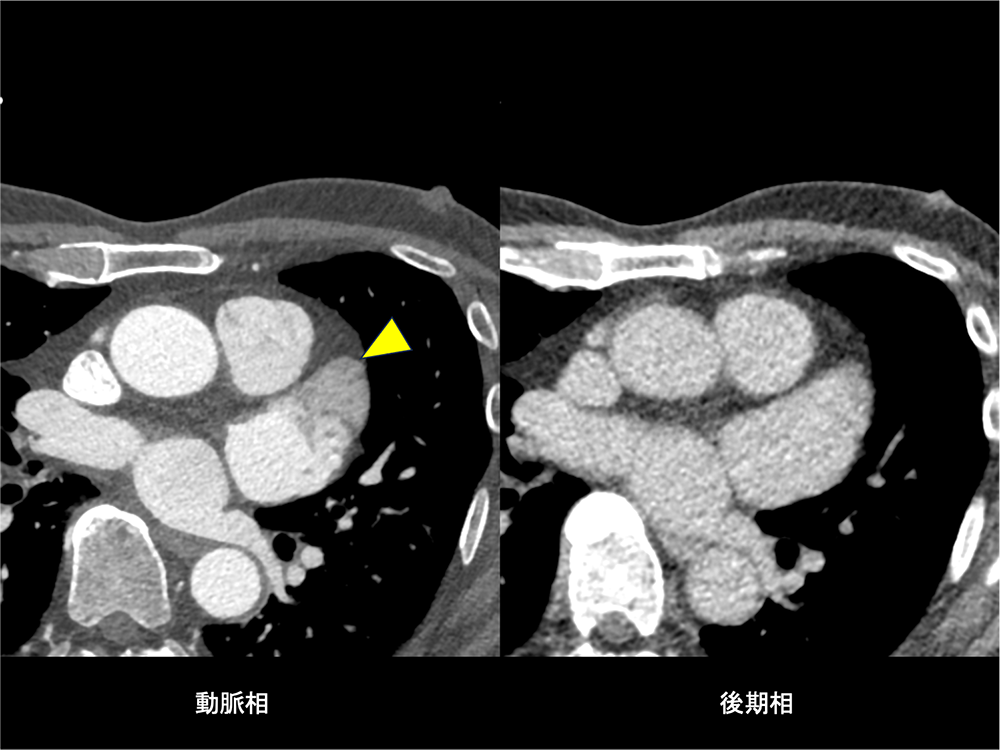

図5.左心耳遅延相(血流うっ滞)

動脈相で左心耳に造影不良域を認めるが、後期相で造影されており、血流鬱滞と診断する。